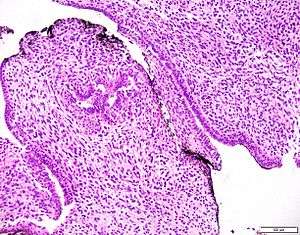

| Prostatic stromal tumour of uncertain malignant potential. H&E stain. | |

Prostatic stromal tumour of uncertain malignant potential, abbreviated PSTUMP, is a rare tumour of the prostate gland stroma that may behave benign or like cancer, i.e. malignant.